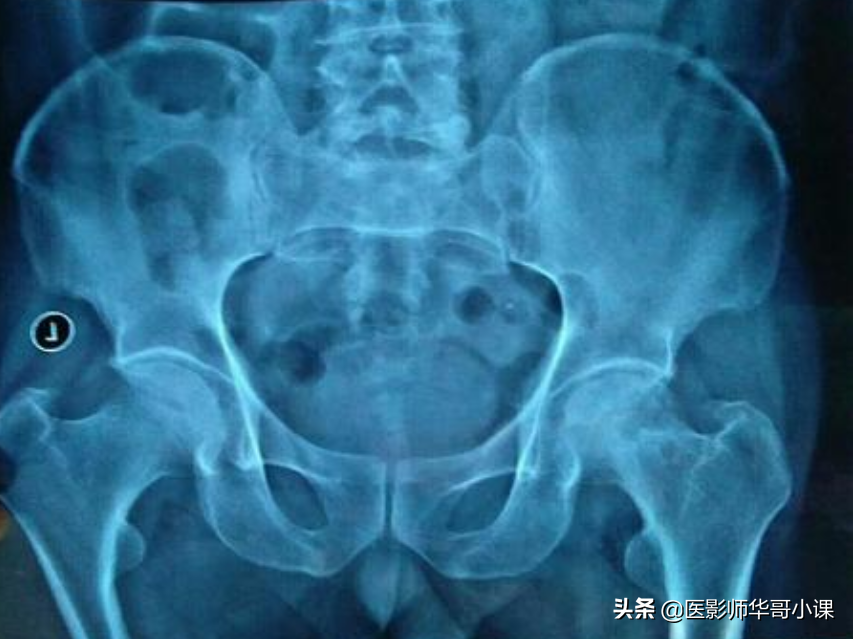

第六节 大腿与髋

尺骨桡骨怎么区分,怎样分辨尺骨和桡骨(骨关节记忆要点,请收藏)

1.股骨头圆韧带窝,在髋关节正位片上表现为股骨头顶部小半圆形骨质缺损,在旋转屈曲位时,股骨头中心部有空洞。

2.股骨颈偶可见环形阴影,为软骨岛。该影内可见重叠的松质骨结构,切勿误为病理变化,在正常的壮年人中,股骨远端背内侧壁皮质有局限性,对称性外壁增厚,也不可误认为病理情况。

3.股骨大小转子的化骨核可为多个,形态可不规则。

4.在股骨大转子外或上可有滑囊钙化,亦称腱鞘钙化。

5.在不标准的股骨近侧位片上,小转子可能和股骨干重叠形成三角形密度减低区,颇似骨破坏。

6.臀肌粗隆线在股骨侧位片上,股骨上段后面臀肌粗隆呈凹凸粗糙不整或较光滑,是臀大肌的附着点,为正常变异,不要误为骨膜增生。

7.小儿的髋关节诸骨,因软骨较厚,关节腔显得较宽,各骨间距离亦较远,所以有时很难肯定是否为髋关节脱臼,尤其在投照时,若两下肢的位置不对称,一侧稍外旋,股骨显得较短,可能误认为脱臼,Shenton氏线有助于鉴别。

8.2~4岁小儿的髋臼边缘高低不平,欠规则。10岁以后逐渐趋向整齐。在正位片上,14~18岁时髋臼外缘可能出现多余的化骨核,呈三角形或卵圆形,有时可分裂成3~4个小块,称髋臼小骨。

9.髂嵴在初生时是光滑的,2~3岁变为不规则,青春期出现二次化骨核,这些化骨核往往不整齐或呈分节状。

10.在髂骨翼部有时可找到放射状及“丫”形血管沟阴影。

11.肠内气泡和髂骨重叠,好象是骨质破坏。

12.髂角为发自髂骨翼向上向生突出的骨质隆起,为多种内胚层或外胚层发育缺陷之一。

13.骶髂关节骶侧的二次骨化中心,多于15~16岁出现,此时关节面略呈模糊并增宽,系正常变异,不要误为病变。

14.骶骨下切迹,骶骨下部一侧或两侧有局限性骨凹陷,深度不一,两侧往往不对称,很象骶骨肿瘤。

15.骶髂关节旁沟即解剖学上的耳前沟,位于小骨盆腔后缘,骶髂关节下方髂骨侧表现为半圆形或浅弧形切迹,为骶髂韧带附着处,也是女性骨盆特征之一,此切迹有时也可出现于骶髂关节的骶骨侧。

16.坐骨结节的二次化骨核有时不完整,呈分节状。

17.妇女的耻骨联合在生育前后增宽,可出现透亮裂隙,(潜在关节腔)其出现率达41.5%,偶可见于男性。